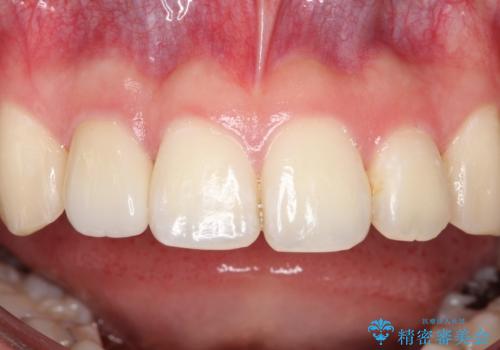

前歯が痛い。根管治療~セラミッククラウン

- 前歯が痛いことを主訴に来院されました。

顕微鏡やラバーダムを使用した根管治療を行ってくれる病院を探していたそうです。

根管治療を含め、オールセラミッククラウンにて修復治療を行っております。

今回は歯冠修復にe-maxプレスクラウンを使っています。